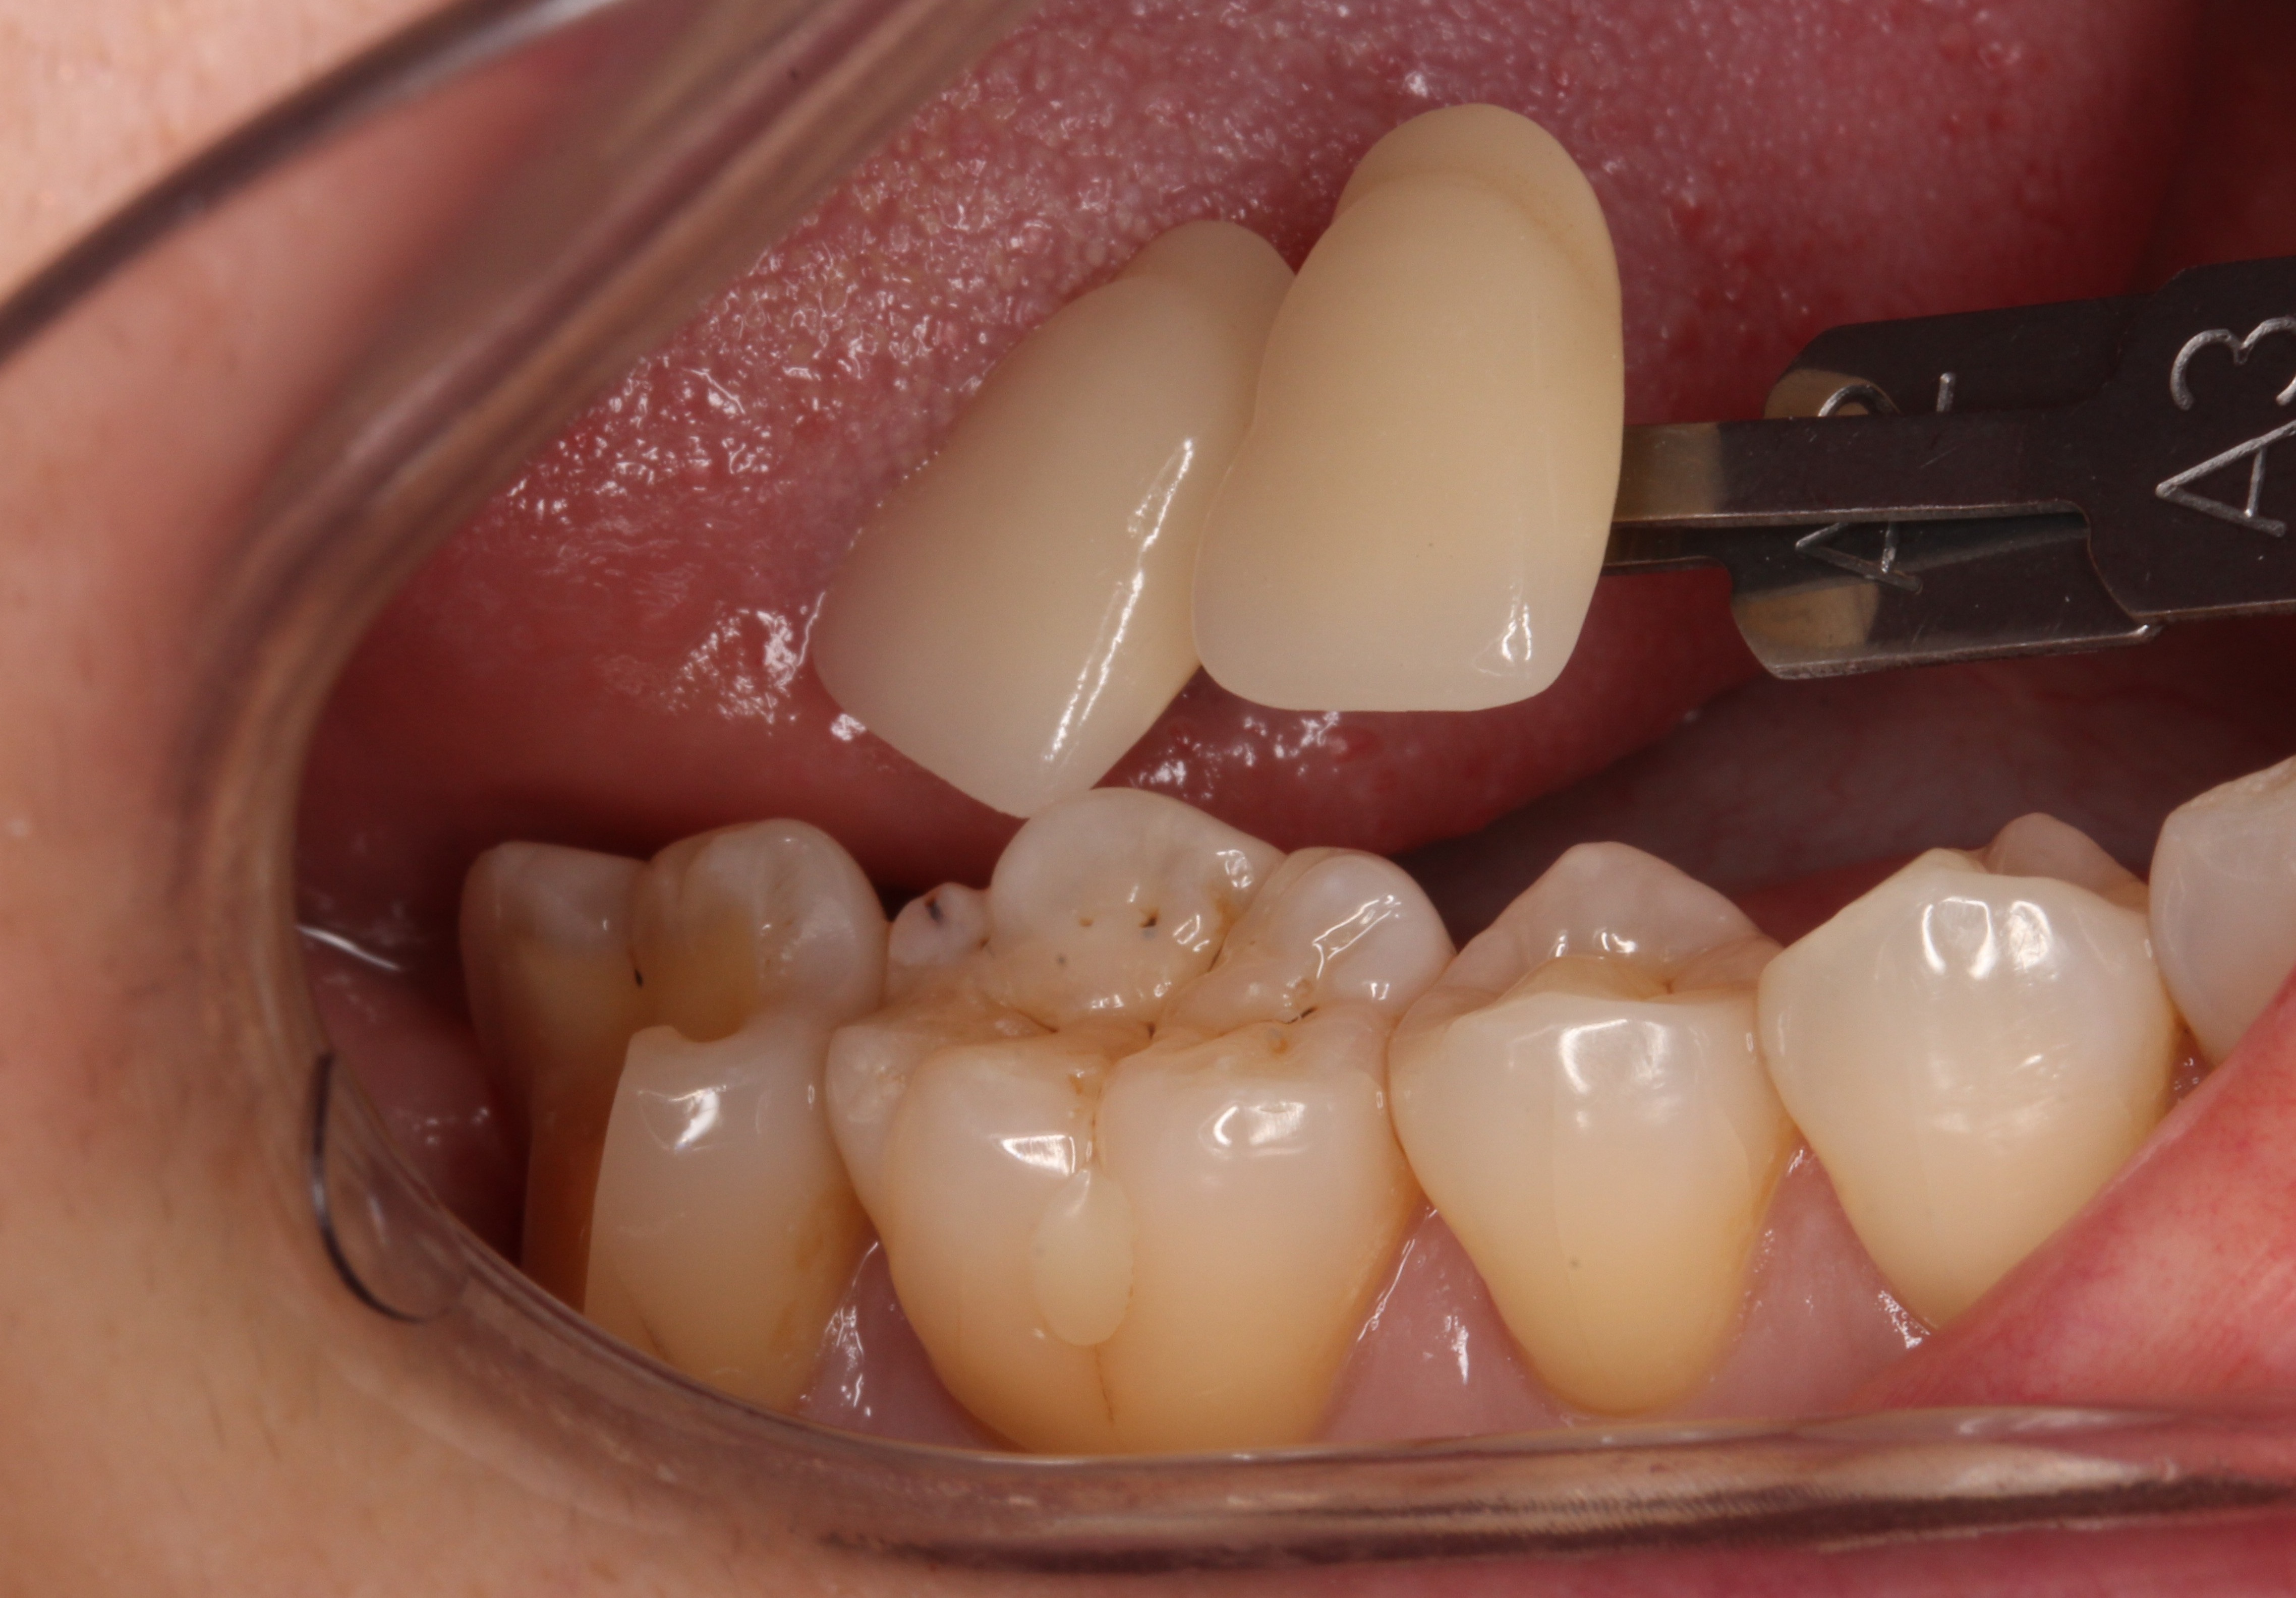

歯の形を整えたところです。

親知らずの穴も埋まってきているのが分かります。

時間はかかりますが、傷口は綺麗に治ってきます。

後は、歯の色を記録して

削ったところにセラミックをセットしていきます。